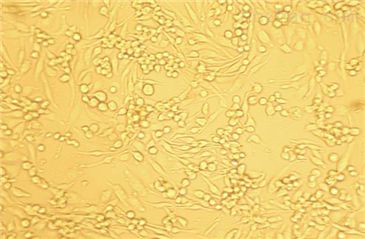

5)细胞生长方式:铺路石状细胞,不规则细胞,贴壁培养。

肺泡组织是机体暴露于外界环境的大表面,哺乳动物肺脏由40多种不同类型细胞组成Ⅱ肺泡上皮细胞,为小的,立方形细胞,胞体较小,核圆,占上皮细胞的60%左右,占所有肺细胞的15%左右,但仅覆盖5%的肺泡表面。处于小内皮和间质细胞、大的巨噬细胞和Ⅰ型细胞之间。